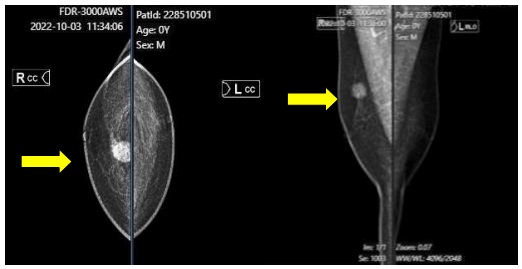

- X-Quang tuyến vú: Khối vùng vú phải BIRADS 5. Hạch hố nách phải.

Hình 2. X-Quang tuyến vú: Vị trí 12h có khối tăng đậm độ kích thước 21x17mm, bờ tua gai, có dải tăng đậm độ hướng về núm vú (mũi tên màu vàng).